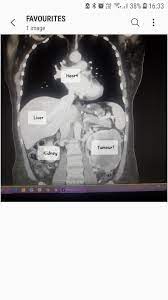

Stomach cancer, also known as gastric cancer, can affect any part of the stomach. He also had a problem with bleeding gums as he grinds his teeth at night, this is apparently a sign of some kind of kidney disease. On the way to the ct scan he ordered, i told my husband, 'this must be what cancer feels like, i'm in so much pain.' the scan showed a shadow on her liver. I'm dying of stage 4 stomach cancer. Unlike many young women, however, my ibs. Lymph nodes are collections of immune system cells. The cancer may now be in all layers of the stomach, as well as other organs close by, like the spleen or colon. Eva katalin kondoros / getty images. Pancreatic cancer is a tricky cancer to identify. Like pancreatic cancer, it may have already. Understandably, this can terrify women. In some cases the tumor may be pressing on a nerve, causing a constant burning pain. Had a ct, mri, bloods and ogd.

Or the cancer could release substances that change the way the body makes energy. He is 6 months cancer free right now. Understandably, this can terrify women. Your stomach receives and holds the food you eat and then helps to break down and digest it. In its early stages, lung cancer doesn't typically have symptoms you can see or feel. It really is a great app and makes me feel like i am in the room with my folks. Some women report feeling a pulse in their stomach when they're pregnant.while this might feel like your baby's heartbeat, it's actually just the pulse in your abdominal aorta. But for many sufferers, pain is not among the early warning signs of stomach cancer. About half of soft tissue sarcomas start in an arm or leg. I suddenly became nauseated, rapidly losing weight, constipated, and felt awful. I don't have a family history of colon cancer. I'm dying of stage 4 stomach cancer. I just didn't feel right.

Ob Gyns Are Using Reddit To Help People Who Desperately Need Advice from img.buzzfeed.com I used to have the same issues like you when it was at its worse for me. Bone pain is the most common type of discomfort associated with cancer. The stomach is a muscular sac located in the upper middle of your abdomen, just below your ribs. Pancreatic cancer is a tricky cancer to identify. This can make those lymph nodes swell. Or, it may be smaller but reach deep into your lymph nodes. Eva katalin kondoros / getty images. Burning pain is also common for those with cancer.